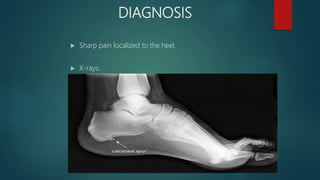

Heel spur PPT